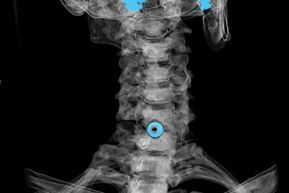

Le diagnostic est établi sur la base des symptômes caractéristiques, en plus d'utiliser :

- Radiographie. La méthode est inefficace, en particulier aux derniers stades du développement de l'ostéochondrose.

- IRM (imagerie par résonance magnétique) de la colonne cervicale. Une méthode qui permet de visualiser les structures osseuses, les hernies discales intervertébrales, leur taille et leur direction de développement.

- Tomodensitométrie. Une solution moins efficace que l’IRM, puisqu’il est difficile de déterminer la présence et la taille des hernies.